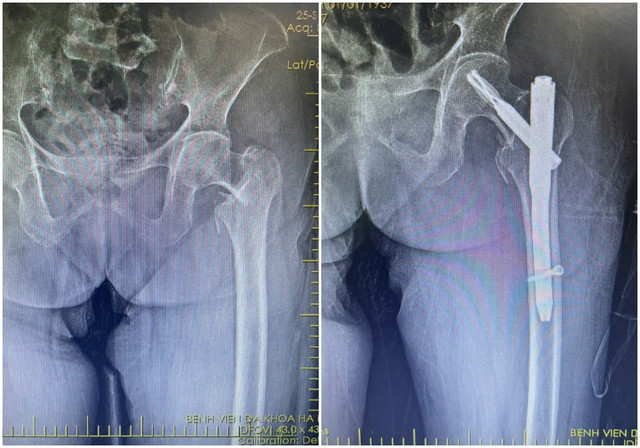

Kết quả chụp X-quang xác định bệnh nhân bị gãy liên mấu chuyển xương đùi. Với tình trạng tuổi cao, sức yếu, việc vận chuyển bệnh nhân hạn chế, tiềm ẩn nguy cơ làm vị trí gãy thêm trầm trọng.

Qua đường rạch da nhỏ khoảng 3-5cm, phẫu thuật viên nắn chỉnh xương gãy về vị trí giải phẫu, sau đó cố định bằng đinh nội tủy PFNA dưới màn hình tăng sáng (C-arm).

Phẫu thuật kết hợp xương ít xâm lấn với đường rạch da chỉ khoảng 3 - 5cm, cho phép nắn chỉnh và cố định vững chắc xương gãy bằng đinh nội tủy dưới sự hỗ trợ của màn hình tăng sáng C-arm. Kỹ thuật này giúp hạn chế tổn thương cơ, mạch máu và mô lành xung quanh, giảm nguy cơ nhiễm trùng, biến chứng sau mổ.